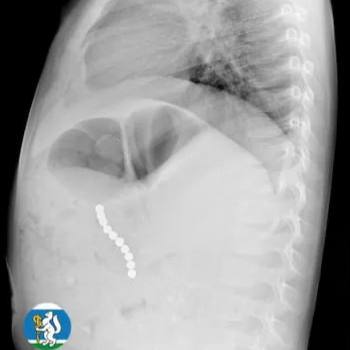

Ульяна почувствовала себя плохо, и родители отвели её к медикам. Те сначала думали о пневмонии. Сделали рентген и на снимке увидели, что в желудке застряла цепочка из магнитных шариков.